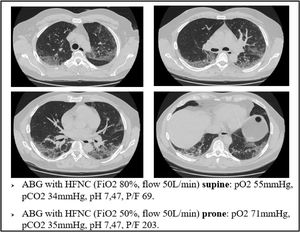

As an example of this phenomenon, we can also report one of our most plain cases of “happy hypoxemia”. Fig. 2 refers to a 67yo woman with no significant past medical history. The CT scan was taken 15 days after the onset of symptoms, and shows bilateral ground glass/crazy paving attenuation, with a visual severity score of 16/20. The patient developed severe hypoxemic respiratory failure and CPAP treatment was started. As displayed on Fig. 2, the patient was tachypneic and ABG during CPAP treatment showed severe respiratory failure. Tidal volume could not be recorded, but we did monitor the swing of esophageal pressure (ΔPes), thanks to a multifunctional nasogastric tube with a dedicated pressure transducer (NutriVent Sidam Group). The swing of esophageal pressure, during spontaneous breathing, reflects the respiratory effort.21 To reduce the confounding factor of breath to breath variability of the respiratory dynamic22, we measure esophageal pressure swing in at least two daily 3 min long recordings at rest and then calculate an average ΔPes. In this case, we measured a ΔPes of 6cmH2O: a normal respiratory effort, even if the patient had profound respiratory failure with tachypnea.

Our findings suggest that the injured areas of the lung are regions with high blood perfusion and rather normal alveoli, therefore in these areas the V/Q ratio reaches the lowest values. Prone positioning leads to a blood flow redistribution to the less damaged area, and hence to a new balance of the V/Q ratio, increasing arterial oxygen levels (Fig. 3)

Again, we can explain this phenomenon as a matter of V/Q ratio. The increased alveolar pressure given by CPAP might help by inflating the alveoli, thereby squeezing the capillaries next to them, reducing the V/Q ratio inequality (Fig. 5)